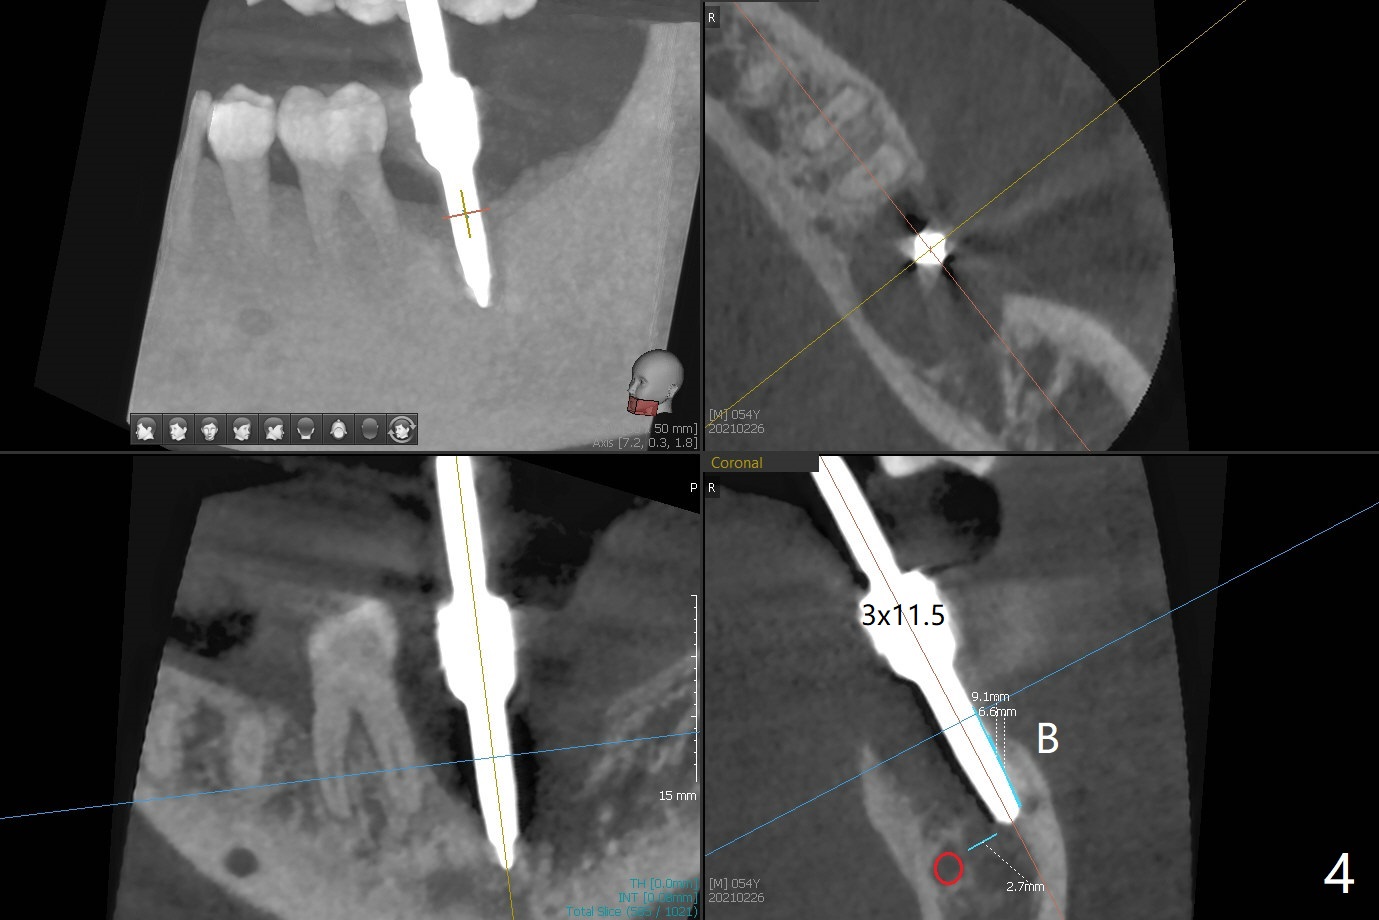

病人回来左下7拔牙植牙,十分感激导板取模后松动牙固位(图一),让他能正常吃饭。去除颊侧树脂和钢丝,6,7之间树脂自动脱落。拔牙后,肉芽组织很多,需要把局麻药注射至肉芽组织中,刮除时不慎远中舌侧牙龈穿孔。尽管纱布压迫,渗血相当多。怀疑导板就位不全,没有纠正。完成钻洞,报废植体无法就位。放置最后一个钻头,根尖片显示钻洞太浅了(图二)。再次磨除6颊侧,远中树脂,导板好像就位,重复钻洞,仍旧太浅(图三),CT表明钻洞偏颊侧(图四)。准备徒手改变钻洞,但是病人疼痛,只好植骨(粘性骨粉)(图五),牙槽窝舌侧,咬合面各覆盖一张PRF膜(图六:箭头),牙间隙维持器和牙周敷料固定。导板在曾经有树脂地方必须缓冲(图七:6;八:*,与图一对比),磨除深度有时不准确。术后两周牙周敷料仍稳定(图九),虽然病人希望撤除,我们偏向保留。反正病人正在做局部牙齿矫正。术后三周牙周敷料脱落,左上6咬合面树脂为了对侧局部牙齿矫正(图十)。骨粉有些丧失(图十一),最好手术时使用不可吸收膜。术后四个月牙槽窝充满骨粉,可以在下齿槽管颊侧植入4x8.5毫米植体(图十二)。